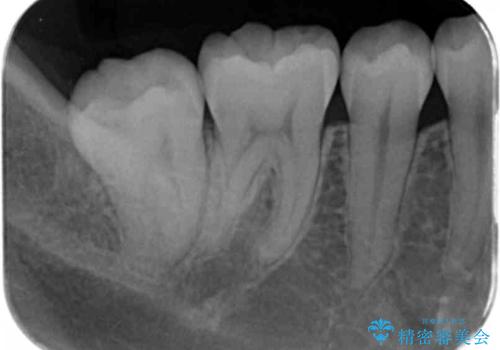

- 奥歯の黒ずみが気になるとのことで来院されました。

樹脂での治療も考えましたが、材料の劣化を避けるためにセラミックインレーでの治療をすることとなりました。

- 右下7 セラミックインレー 77,000円費用は治療当時の料金となります